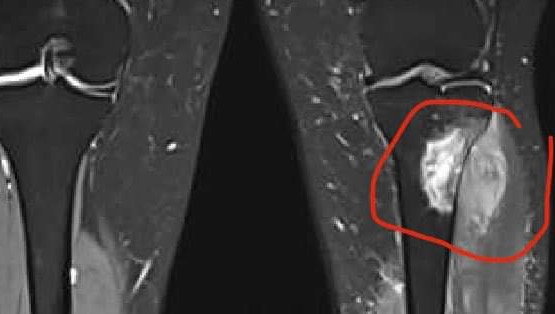

Life definitely changed very quickly for this new family back in Sept/Oct 2023 - a diagnosis of Ewings Sarcoma (rare aggressive bone cancer) in the left lower leg while also being only 3.5 months postpartum to our first baby - we were stunned nonetheless.

Surgery to remove the tumourous bone was scheduled between rounds 6 and 7 but scans revealed that while chemo was having a good affect on the cancer, the tumour had not receded back into the bone and away from the nerves and vessels enough. So no rest for the wicked! We continued on with our fortnightly chemo schedule with no break.

Onwards to the next stage - we find out next week if the surgeon is able to save my leg or amputate. This next stage is big but should be the last in the great scheme of cancer.